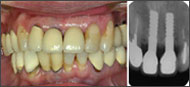

| 審美性考慮前後の比較 |

(7年前頃から審美性を工夫)![]() 右上1は考慮前のもので8Y後、左上1は考慮後のもので6Y 10M後。2005/12/16 |

私は1ピースAQBを植立して17年以上になる。最初の10年近くは口腔清掃性重視で、冠のマージンは歯肉縁ギリギリであった。そのため冠装着後、周囲粘膜が引き締まってくるとチタンの頸部が露出して審美性は劣っていた。当時は口腔清掃性重視からチタンの露出はインプラント補綴の証でもあった。その後インプラントの臨床成績の飛躍的向上にともなって、機能性のみならず審美性も要求されるようになってきた。私もここ7、8年審美性に配慮するようになって、本稿のような工夫で補綴するようになっている。それゆえ1ピースの審美性については、7、8年の予後観察結果で本稿を論じているわけで恐縮の至りではあるが、今後の5年、10年後をさらに経過観察して行きたい。